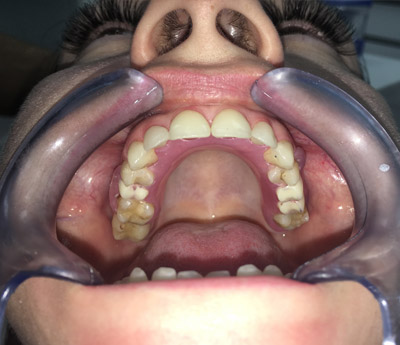

Implantul dentar este un dispozitiv confecționat din titan, care are rolul de a înlocui absența unuia sau mai multor dinți. Implantul îndeplinește funcția de radacină pentru viitoarea coroană dentară. Este fixat după intervențiile pregătitoare.